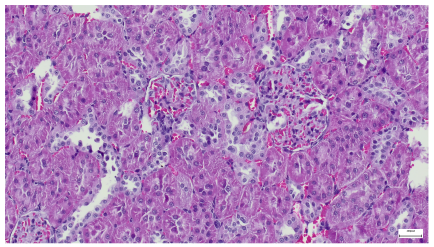

Table 4 below presents histological proof for renal damage in the G-IV group suffering from a dual metabolic impairment, albeit treated with statin.

Table 4.

Histological proof for renal damage in the diabetic-and-obese statin-treated group G-IV.

The histological extent of lesions suggests a definite inflammatory process in the renal matrix and glomeruli, but the extent of the disruptive process as resulting from an average nephron pool loss is limited. This is consistent with the limited duration of our experiment, with definite development of chronic kidney disease taking sometimes as long as 24 weeks. However, expecting this limited extent of damage, we chose a relatively short—proportionate—duration of statin treatment. Our results demonstrate a statistically significant higher retention of creatinine and urea in plasma—a reflection of the respective reduction in renal function—in every single experimental group (G-II to G-IV) in comparison to the control group G-I. The diabetic group G-III demonstrates the highest values for both creatinine and urea across the whole experiment population. The plasma concentrations of retention byproducts in both G-II and G-III are statistically significantly higher compared to the control G-I, indicating that each condition independently leads to important impairment in kidney function. The assumption of concurring actions in a model exhibiting obesity and diabetes simultaneously should translate into outcomes—renal and inflammatory—with values skewed from normality, the dimension of departure from the normal range at least as big as in any of the models exhibiting an individual condition.